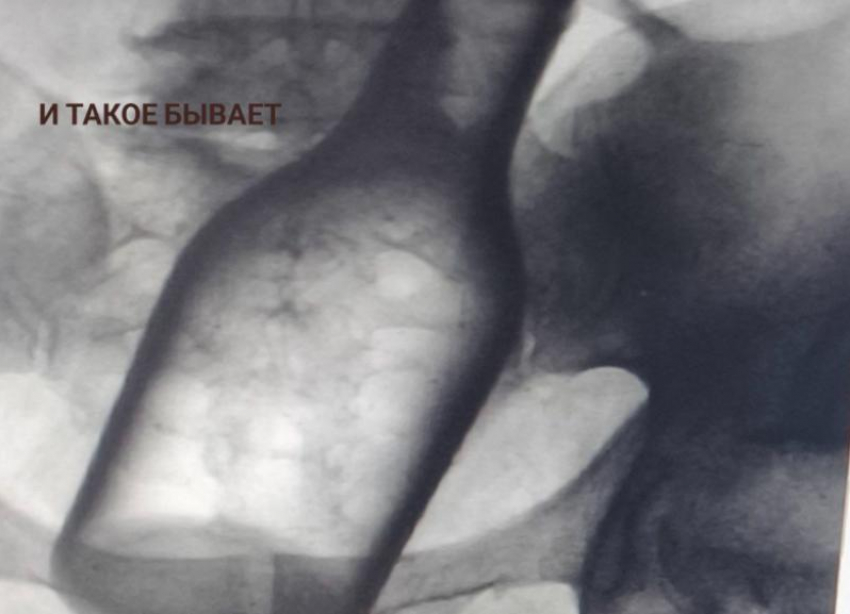

Монета, проволока, бутылка: что извлекали из ставропольских пациентов в 2025 году

Прошлый 2025 год в приемном отделении ГКБ Пятигорска напоминал порой работу следователей или археологов. Только вместо улик или артефактов врачи извлекали из пациентов нечто совершенно немыслимое. Подробности 2 февраля 2026 года рассказали в социальных сетях медучреждения.

Маленькая бутылка, металлическая пластина с шурупами, чей путь в организм остался загадкой, еще коронки, монеты разного достоинства, проволока, фруктовые косточки и батарейки доставали из пациентов.

«Случаи курьезные, но проблема на самом деле серьезная — ежегодно в ГКБ Пятигорска поступают десятки пациентов с инородными телами. Среди них немало детей. И им, как правило, требуется экстренная медицинская помощь», — удрученно констатируют медики.